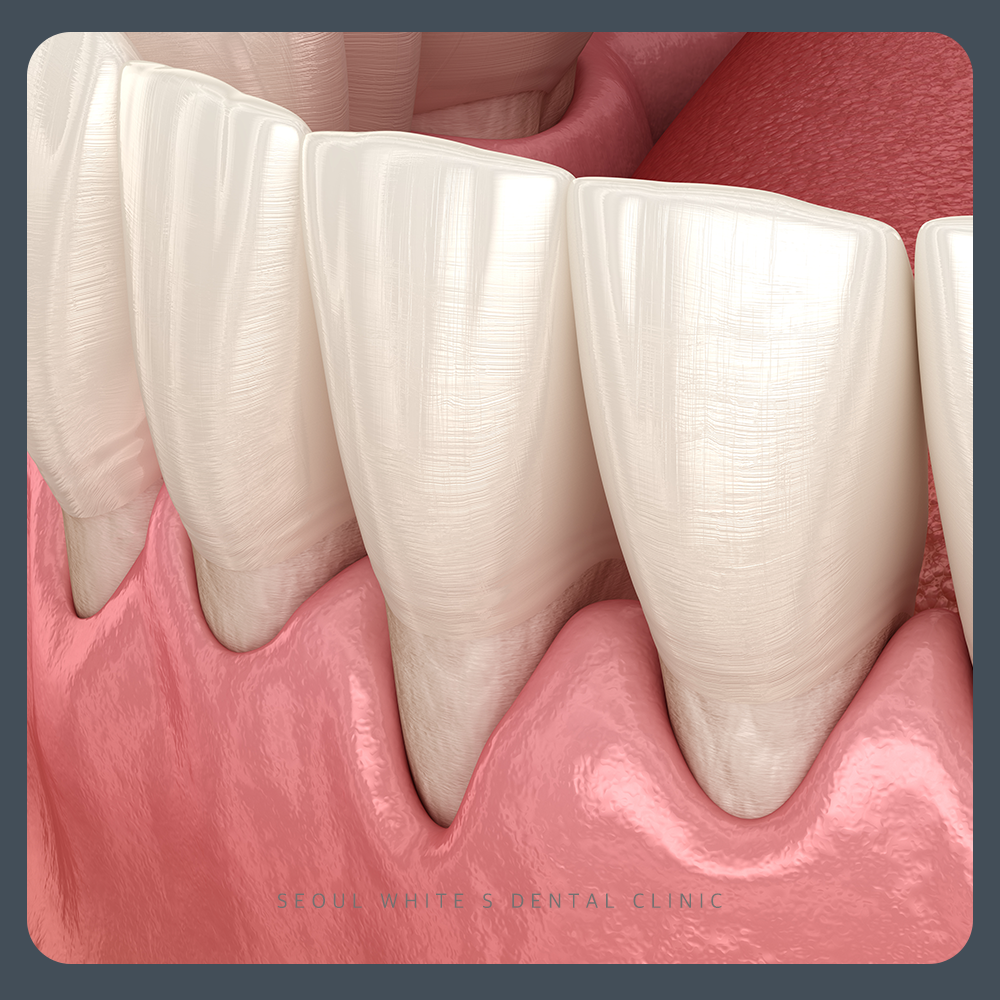

‘치경부 마모증(cervical abrasion)’이란 치아 머리의 뿌리 방향 잇몸경계부위의 ‘치경부’라는 부분이 마모되어 치질의 결손이 발생하는 질환을 의미합니다.

잇솔질은 환자분의 구강 상태에 따라 차이가 있으나, 일반적으로 치질이 손실되지 않는 회전법으로 잇솔질 하시기를 권장드립니다. 만약, 좌우로 세게 밀면서 닦으면 치질이 마모되는데요. 이러한 방법은 치경부 마모증을 야기할 뿐만 아니라, 치아도 깨끗하게 닦이지 않게 됩니다. 따라서, 잇솔질은 올바른 방법으로 치아의 치태(plaque)를 제거하셔야 하며 잇솔질을 세게하는 것은 지양하시길 바랍니다.

평소 자신도 모르게 치아를 꽉 무는 습관이 있거나 긴장이 되면 이를 세게 무는 분들과 취침 시 이갈이를 오래 하시는 분들에게서 ‘치경부 마모증’이 많이 발생합니다. 지속적으로 치아에 힘이 가해지면 치아에서 가장 얇은 부위인 치경부가 패이거나 깨지는 현상을 보이게 되는데요. 이러한 습관은 자신의 의지로 교정되기 어려운 부분이 있으므로 반드시 치과에서 이갈이 장치나 교합 조정등의 치료를 받으시길 바랍니다.